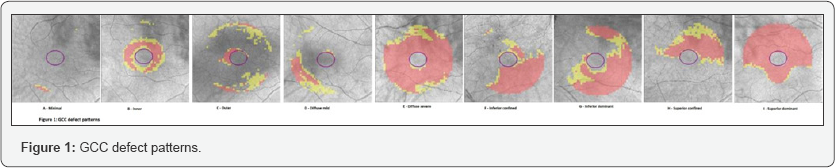

GCC deviation map was used to determine GCC defect patterns. Abnormal GCC thickness in the deviation map is shown by yellow and red at the %5 and %1 levels, respectively. The abnormal area deliniated manually and its area measured using the Image J programme (version 1.47). Areas were summed when there were multiple abnormal areas. Measured values were converted to the values fit to the scan area of the deviation map which was a elliptical annulus area on the 6x6 mm 2 square area of the macular scan. GCC defect patterns were classified as minimal, inner, outer, diffuse mild, diffuse severe, inferior confined, inferior dominant, superior confined and superior dominant. The inner defect was defined as circumferential GCC defect within vertical inner and outer radii of 0.5 and 1 mm and within horizontal inner and outer radii of 0.6 and 1.2 mm from the fovea, respectively. The outer defect was defined as a circumferential GCC defect outside a vertical radius of 1 mm and horizontal radius of 1.2 mm from the fovea. The diffuse mild defect was defined as a general yellow or red pattern in less than half of the scan area without hemifields preponderance. The diffuse severe defect was defined as as yellow or red colour pattern seen in more than half size of the scan area without hemifield preponderance. The inferior confined and superior confined defects were defined as yellow or red colour patterns in only the corresponding hemifield. The inferior dominant and superior dominant defects were defined as yellow or red patterns exceeding horizontal midline that were dominant in the corresponding hemifield [15]. GCC defect patterns were shown in Figure 1.

In this study GCC defect patterns were classified as minimal, inner, outer, diffuse mild, diffuse severe, inferior confined, inferior dominant, superior confined and superior dominant. Tan et al. [32] reported that macular inner nuclear layer loss was more significant in inferior perifoveal region in perimetric and preperimetric glaucoma patients [32]. Kotera et al. [39] reported that inner retinal layers were thinner especially in inferior quadrant than superior quadrant and in temporal quadrant than nasal quadrant in glaucoma suspects and preperimetric glaucoma patients than healthy individuals [39]. Hood et al. [40] reported that ganglion cell plus inner plexiform layers were thinner in the inferior region in glaucoma patients [40]. Jeong et al. [15] showed that in mild and moderate stage POAG patients the inferior confined type ganglion cell patterns was more frequent, in advanced stage POAG patients diffuse severe type ganglion cell pattern was more frequent [15]. We found that GCC defect patterns were not significantly different between XFG and POAG. The most frequent GCC defect pattern was the diffuse severe type in XFG and diffuse mild in POAG. Diffuse type GCC defects were more frequently seen in both groups than localized defects like inferior confined, inferior dominant, superior confined and superior dominant. But in advanced glaucoma GCC defect patterns were significantly different between XFG and POAG, diffuse severe type GCC pattern defect was the most frequently observed in XFG and more frequent in XFG than POAG. As the severity of glaucoma increased, GCC pattern defect tended to be more severe in XFG than POAG.